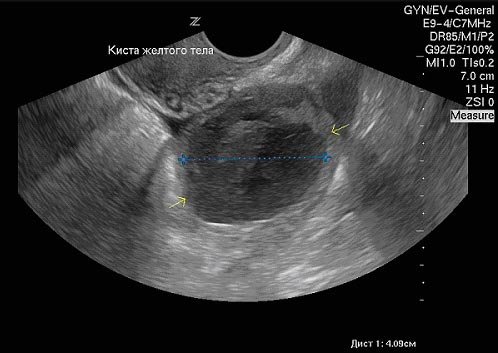

вот так выглядит желтое тело

оно обычно серого цвета с неровными краями.